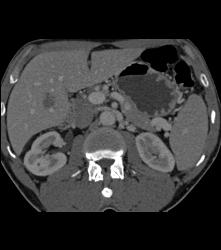

Infarcted Left Kidney Due to Stenosis of Upper Pole Renal Artery